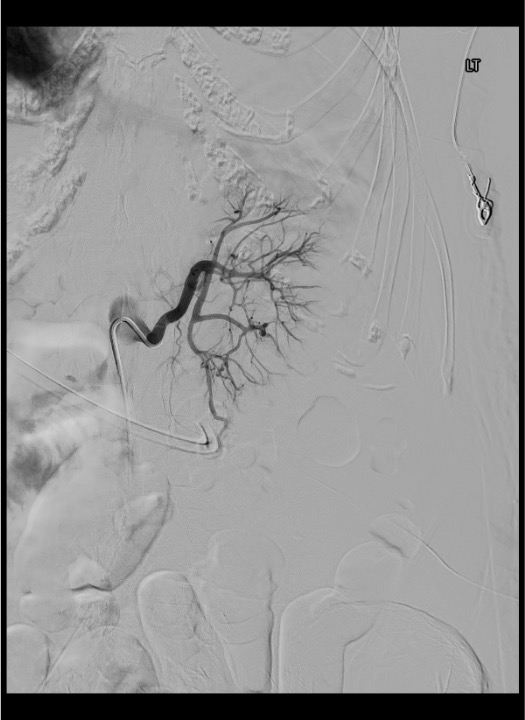

On flush aortogram, identify renal artery origins at L1–L2 (tennis racket or Omni-Flush catheter positioned with tip just above renal artery origins). Selective renal angiogram defines anterior/posterior division and segmental branches. In the nephrographic phase, assess for parenchymal defects (prior infarcts), mass effect (tumor), and early venous filling (AVM/AVF). Superselective catheterization into the feeding segmental or interlobar artery using microcatheter allows precise identification of the target lesion before embolization.

Selective Renal Artery Catheterization

Superselective Catheterization

Embolization

Completion Angiogram